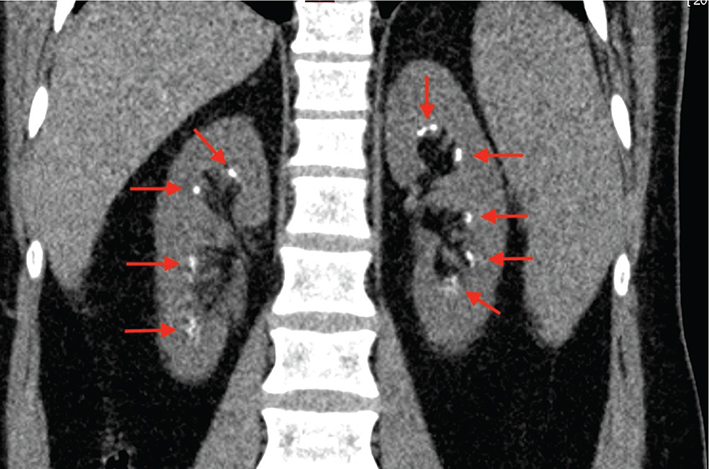

A 27-year-old male was referred to Oral and Maxillofacial Surgery at Uppsala, Sweden, for dental care (Figure 1a–h).

Figure 1. (a–g) Initial dental examination with orodental phenotypes associated with ERS.

Dental diagnostic assessment and interpretation

The dentition included yellow and worn permanent and deciduous teeth surrounded by hyperplastic gingiva. The bite displayed a retrognathic maxilla, bilateral open bite, bilateral crossbite, elongated lower molars and thin alveolar bone where teeth were missing. The radiographical examination (orthopantomogram and intra oral conventional radiography) revealed thin enamel, impacted teeth, intra-pulpal calcifications, internal resorption, localised aggressive marginal periodontitis and apical periodontitis. A tentative diagnosis of syndromic AI was made.